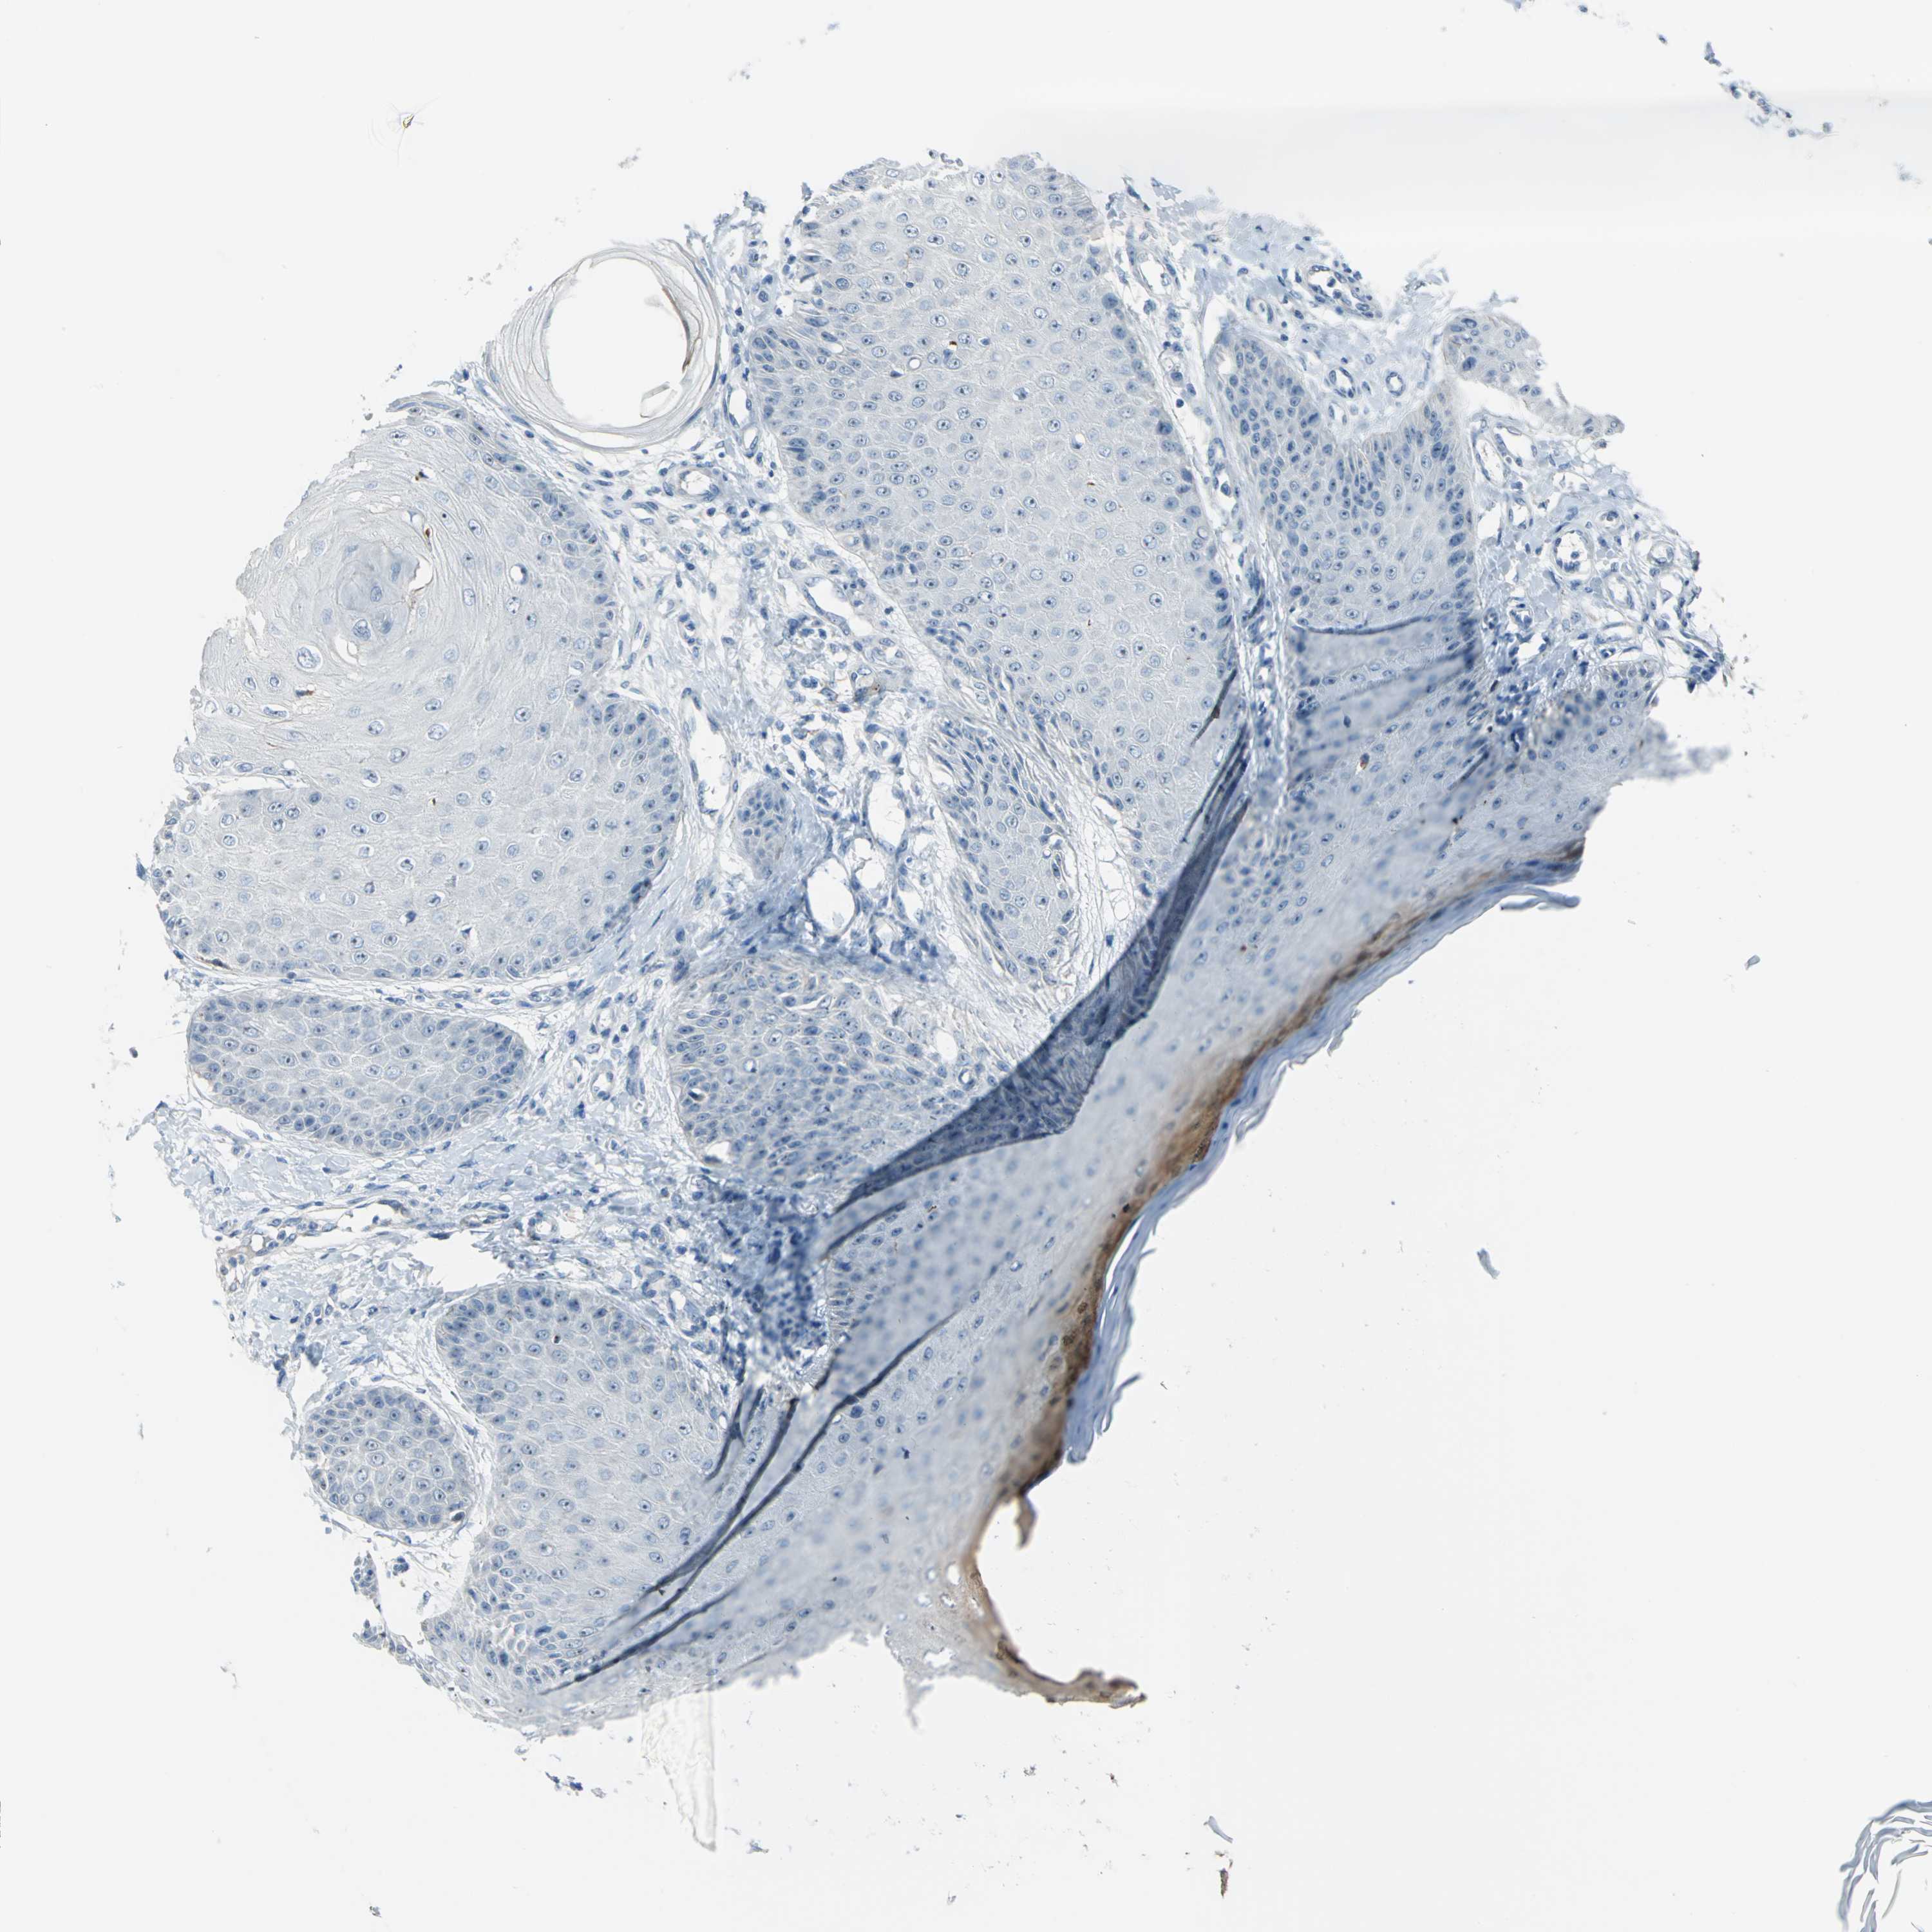

SKIN CANCER - Protein expressioni

A mouse-over function shows sample information and annotation data. Click on an image to view it in a full screen mode. Samples can be filtered based on level of antibody staining by selecting one or several of the following categories: high, medium, low and not detected. The assay and annotation is described here.

Antibody stainingi

Antibody staining in the annotated cell types in the current human tissue is reported as not detected, low, medium, or high, based on conventional immunohistochemistry profiling in selected tissues. This score is based on the combination of the staining intensity and fraction of stained cells.

Each image is clickable and will lead to virtual microscopy that enables deeper exploration of all samples and also displays staining intensity scores, fraction scores and subcellular localization as well as patient and tissue information for each sample.

Antibody HPA005895

Antibody CAB013536

Squamous cell carcinoma, NOS

Basal cell carcinoma